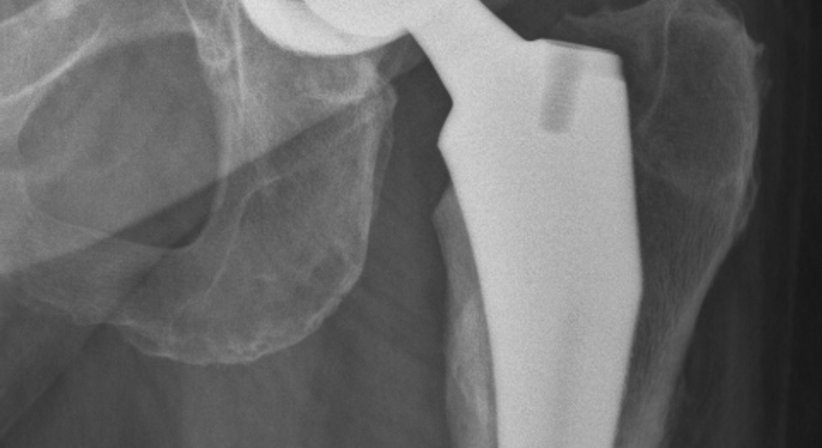

Wahl der Hüftprothese und des Operationzugangs

(minimal-invasive Hüftoperation nach der AMIS © - Methode)

Es stehen unterschiedliche Prothesen und Operationstechniken zur Verfügung, um das körpereigene Gelenk zu ersetzen. Der Eingriff kann minimal-invasiv oder offen erfolgen. Die minimal-invasive Methode bietet Patienten einige Vorteile, allen voran, dass die Muskulatur seitlich der Hüfte bei der Operation nicht durchtrennt wird. Dadurch werden Vernarbungen und Heilungsschmerzen an diesen für die Fortbewegung wichtigen Muskeln vermieden, was im Regelfall eine kürzere Rehabilitationszeit bedeutet. Patienten sind nach der Operation schneller wieder selbstständig mobil und können alltäglichen und sportlichen Aktivitäten wieder früher nachgehen. Welche Prothese und Operationstechnik im Einzelfall am besten geeignet sind hängt von der Ausgangssituation des Patienten und individuellen Faktoren ab. Sind die Voraussetzungen gegeben, dann führe ich Hüftimplantationen bei Möglichkeit minimal-invasiv (AMIS © - Methode) durch.